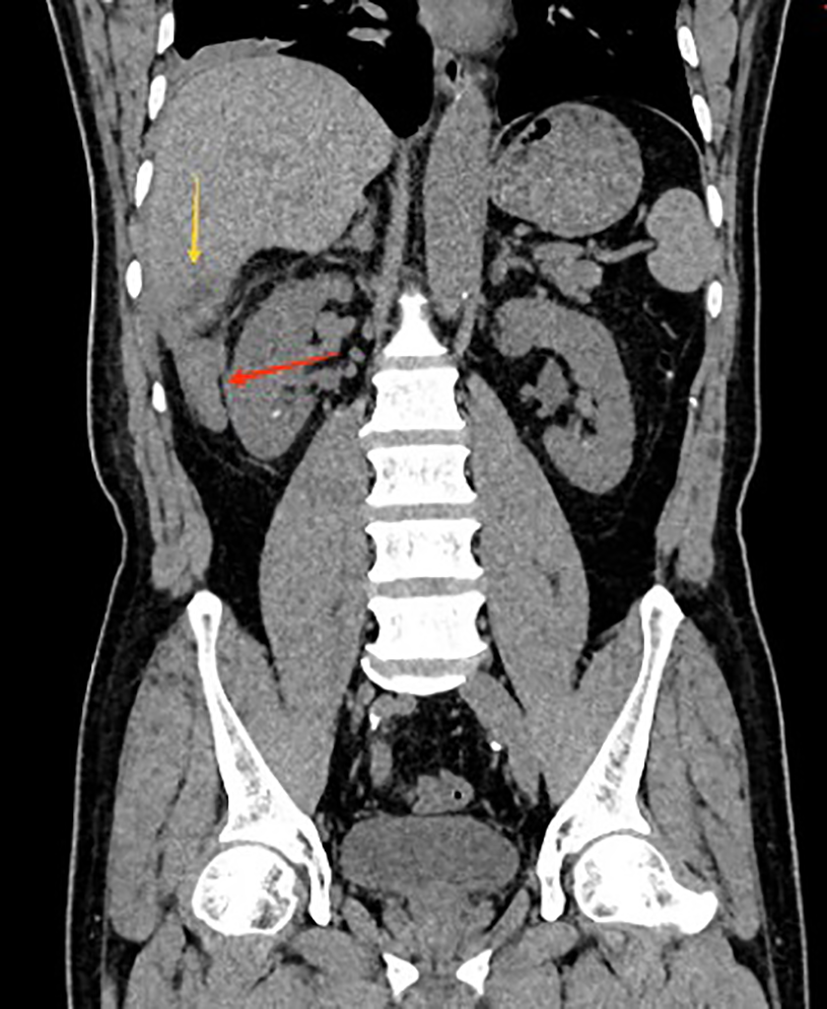

A 56-year-old male patient was admitted to the hospital on February 28, 2025, with the chief complaint of “right abdominal pain accompanied by fever for 2 weeks.” Two weeks prior, the patient developed right abdominal pain without any obvious trigger, which persisted and was unrelieved, accompanied by fever, with a maximum temperature of 39°C. He did not experience chills, had cloudy urine, but did not report urinary frequency, urgency, dysuria, nausea, vomiting, or diarrhea. The patient has no history of night sweats, no recent weight loss, and no previous symptoms of chronic abdominal pain. The patient had a body mass index (BMI) of 29.4, with no history of smoking or alcohol consumption. He had no significant past medical history and reported no known familial or hereditary disorders. The patient sought medical attention at a local hospital, where a urinary system CT(Computed Tomography) scan revealed bilateral kidney stones. He was diagnosed with “bilateral kidney stones complicated by urinary tract infection” and was treated with cefotaxime for 10 days, but his pain did not show significant improvement. He later presented to our emergency department, where a non-contrast abdominal and pelvic CT scan (Figures 1, 2) revealed acute appendicitis (subhepatic appendix) and a hepatic abscess in segment VI measuring approximately 22 mm × 29 mm. He was admitted to our department for further diagnosis and treatment.

Figure 1

Coronal CT showing subhepatic appendicitis (red arrow) with associated hepatic abscess in segment VI (yellow arrow).